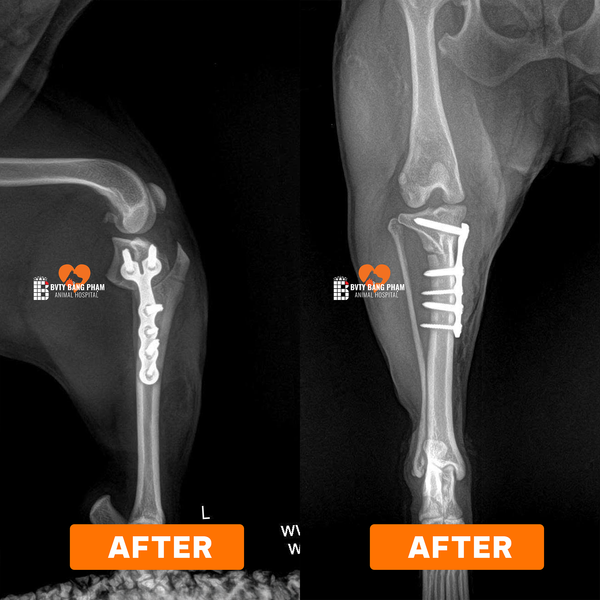

DỊCH VỤ PHẪU THUẬT TPLO – ĐIỀU TRỊ ĐỨT DÂY CHẰNG CHÉO CHO CHÓ MÈO

Phẫu thuật TPLO (Tibial Plateau Leveling Osteotomy) là kỹ thuật chỉnh hình tiên tiến hàng đầu trong điều trị đứt dây chằng chéo trước (CCL) ở chó, giúp ổn định khớp gối và phục hồi khả năng vận động tự nhiên cho thú cưng.

Tại Bệnh viện Thú y Bằng Phạm, các ca phẫu thuật TPLO được lên kế hoạch chính xác bằng phần mềm iBlueVet của BlueSAO – cho phép bác sĩ mô phỏng phẫu thuật trên hình ảnh X-quang trước khi mổ, xác định các thông số tối ưu như TPA, góc xoay, kích thước lưỡi cắt và loại nẹp cố định.

Trong mổ, ekip phẫu thuật sử dụng bộ dụng cụ TPLO của BlueSAO – công nghệ ren kim loại truyền thống có độ bền vượt trội, ổn định lâm sàng cao và tuổi thọ dài, đảm bảo kết quả điều trị bền vững.

Trực tiếp phụ trách kỹ thuật là Giám đốc Phạm Bằng, được đào tạo và chứng nhận quốc tế trong lĩnh vực phẫu thuật chỉnh hình thú y của BlueSAO, chuyên sâu về TPLO, TTA, và các kỹ thuật phục hồi chức năng khớp nâng cao.

Mỗi ca mổ đều được thực hiện trong phòng phẫu thuật tiêu chuẩn quốc tế, có C-Arm hỗ trợ theo dõi tiến trình phẫu thuật theo thời gian thực, giúp kiểm soát chính xác vị trí cắt xương và đặt nẹp.📞 Liên hệ khám & tư vấn